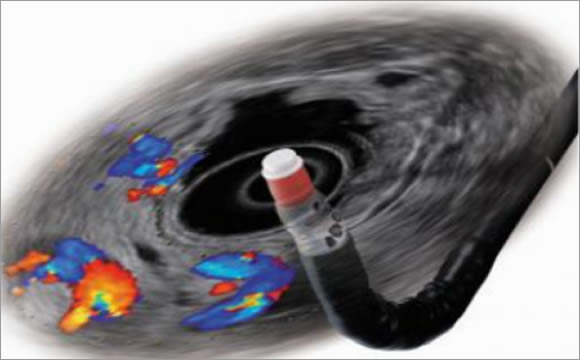

Endoskopik ultrason (EUS), aşağıdakileri harmanlayan özel bir işlemdir:

Endoskopi— Sindirim sistemin iç yüzeyine bakmak için ucunda kamera olan esnek cihazın kullanılmasıdır.

Ultrason — Bağırsak duvarının ve yakındaki organların veya yapıların ayrıntılı görüntülerini görmek için yüksek frekanslı ses dalgalarının kullanımıdır.

Endoskopik Ultrasonografi (EUS) hem sindirim sisteminin iç yüzeyini görür, hem de duvarın katmanlarını ve duvarın arkasındaki organları görür. Bir anlamda EUS duvarın arkasını görebilmektir.

EUS cihazı, kameralı ve ucunda ışık olan ince, esnek bir tüptür. Cihazın uç kısmına küçük bir ultrason probu eklenmiştir.